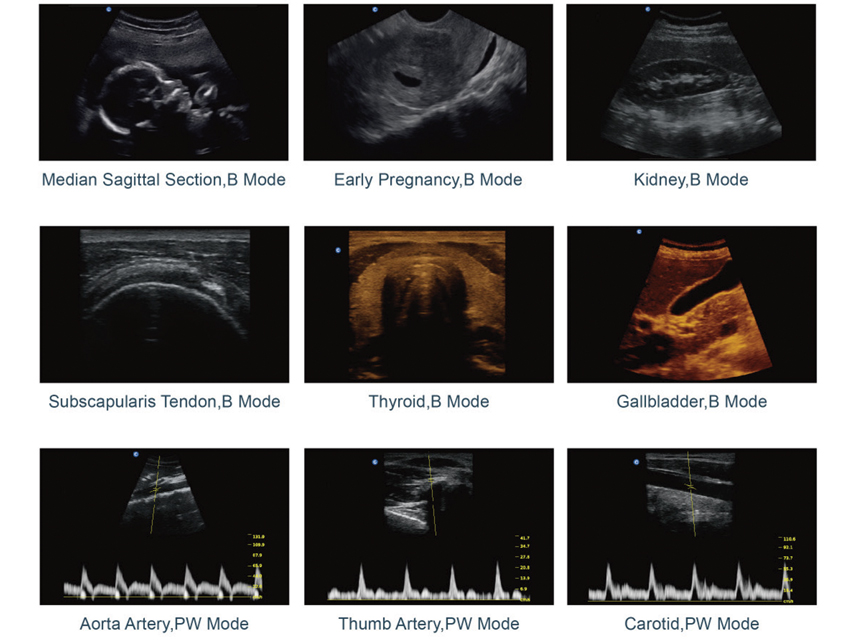

Display and image processing modes

B, B/B, 4B, M, B/M, PW (ECO2, ECO3EXP. only) multi-frequency imaging.

Image processing

- composite images - trapezoidal

- intelligent I-image optimisation - automatic PW

- THI (Harmonic Tissue Imaging) (ECO2, ECO3EXP. only)

- SRA (focal spot reduction algorithm) - Chroma

- digital beam-former system - AIO (Optimisation

- full screen display Automatic image)